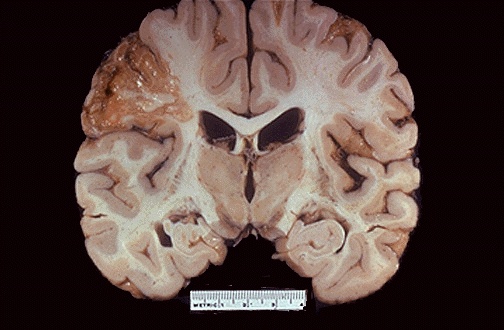

Grossly, the cerebral infarction at the upper left here demonstrates liquefactive necrosis. Eventually, the removal of the dead tissue leaves behind a cavity.